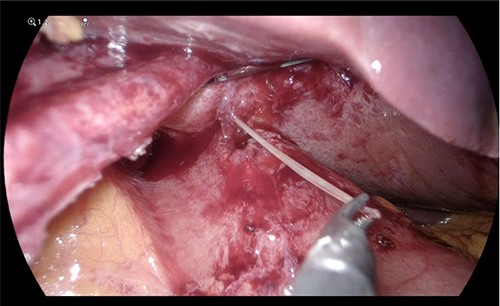

On laparoscopy, the left lateral segment of the liver was adherent to the gastric antrum (Fig. 2). Adhesions between the liver and stomach were divided with blunt and sharp dissection. The fishbone was pulled out of the liver intact and extracted through the port. The abscess was opened, drained and washed. A sealed fistulous tract was identified at the antrum; this was repaired with an omental patch. The patient had an uneventful recovery and was discharged the following day.